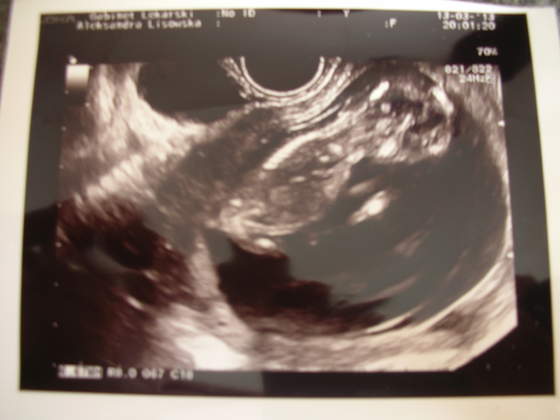

"Zmolestowałam" moją Panią doktor, żeby "skoro już tu jestem" zrobiła mi usg - tak na uspokojenie nerwów chciałam zobaczyć, że serduszko puka. Pani doktor się zgodziła (pomimo iż już miała 30 min opóźnienie w kolejce, a formalnie wskazań nie było, bo widziałyśmy się niedawno i brak krwawień, itp). Podpatrzyłam sobie bobaska, a pani doktor przy okazji wymierzyła wszystko dokładnie (i tak chcąc, nie chcąc trafiłam przypadkiem na badanie przesiewowe, "bo skoro już tu jestem" ;-)). Wszystko w normie, bobasa podpatrzyłam z wszystkich możliwych stron i wyszłam z gabinetu bogatsza o dwa zdjęcia:

Według usg bobas ma 67 mm, czyli 13t0d oraz termin 18.09.2013.

(Z pytaniami o płeć czekam do 16 tygodnia, teraz to wszystko zbyt podobne do siebie.)